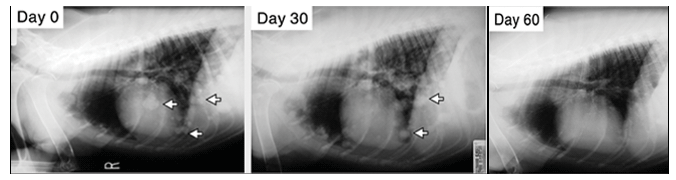

Signalment: Canine, Labrador Retriever cross, 8 years/4-month-old, male castrated, 52.4 lbs.